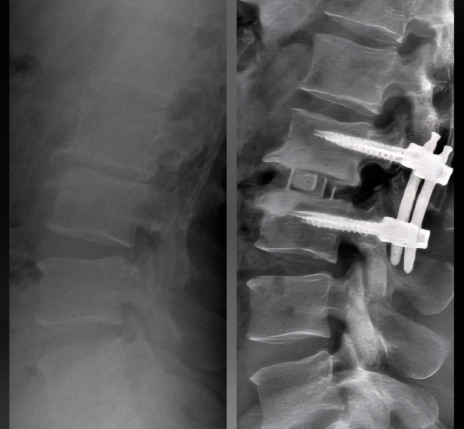

ESPONDILOLISTESE

O escorregamento de uma vértebra sobre a outra pode ser de causa congênita ou adquirida, pode causar dor na coluna ou sintomas irradiados para os membros. Podem afetar pessoas jovens, em fase de crescimento, adultos que tiveram espondilolistese na infância e não descobriram, ou idosos que começam a ter o escorregamento da vértebra por motivos degenerativos.

CIRURGIA DE ARTRODESE PARA DOENÇAS DEGENERATIVAS

A fixação das vértebras pode ser feita em qualquer segmento da coluna – cervical, torácica ou lombar. As cirurgias podem ser feitas pela frente, pela lateral ou por trás, ou então, por vias combinadas.

CIRURGIA DE ARTRODESE PARA ESCOLIOSE E OUTRAS DEFORMIDADES

As cirurgias de deformidades são consideradas de alta complexidade, envolvem diferentes técnicas de correção, tanto com uso de parafusos pediculares quanto uso de bandas sublaminares. A equipe cirúrgica conta com o apoio de equipe de neurofisiologistas para a monitorização da medula e dos nervos espinais.